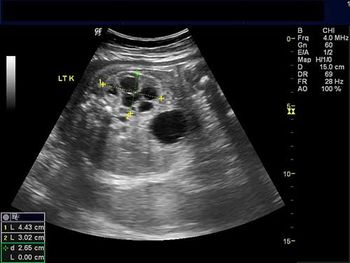

Challenge your diagnostic skills: See anything out of the ordinary in the kidneys of this third trimester fetus?

Ultrasound-based evaluation is less costly than an endometrial biopsy and also allows for evaluation of the adnexa and bladder.